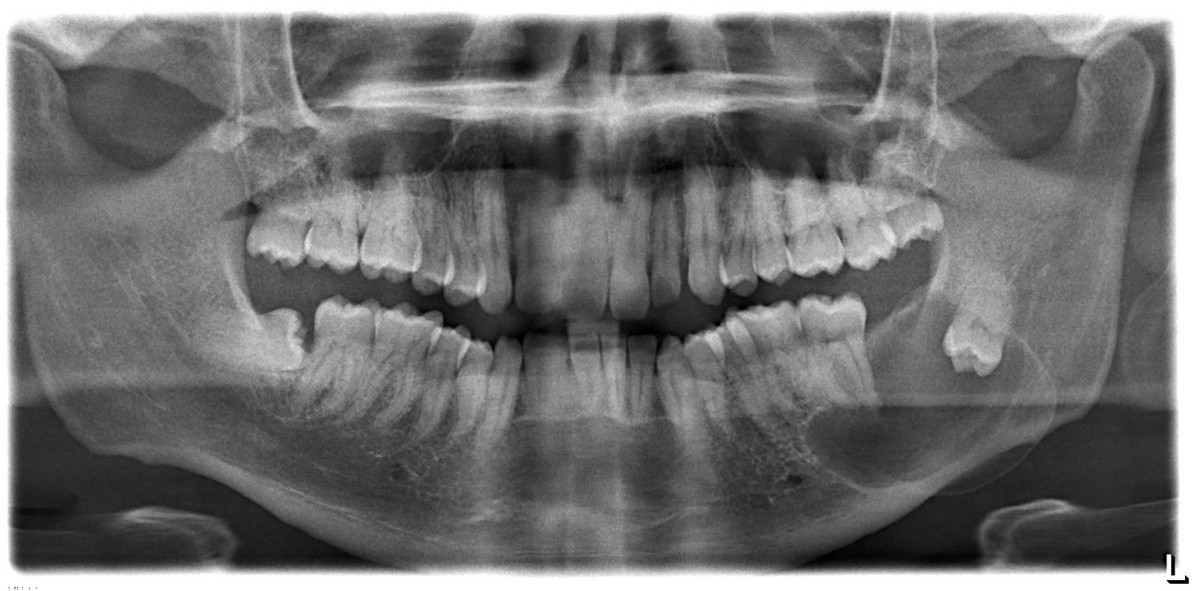

8 / 25

8. (Select ONE correct answer)

What is the most likely diagnosis for the lesion associated with tooth 3.8?